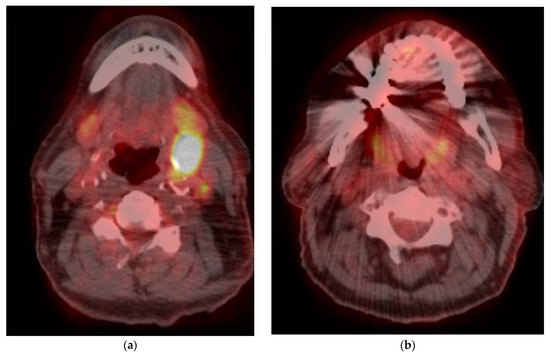

5. Imaging of Oropharyngeal Cancers

8.1. Initial Staging

8.2. Response Assessment